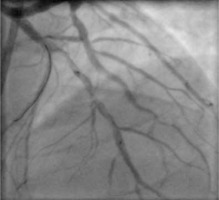

Dissection after predilatation, before BVS implantation, occurred in 22 patients, and in 17 of them it was covered by BVS implantation with optimal angiographic results. Five of them were finally in the dissection group. In another 4 patients from the dissection group, dissection appeared after BVS implantation and required additional intervention, but it was absent after predilatation. The description of dissection according to the NHLBI classification [2] is presented in Table I. Examples of angiographic images of individual dissection classes are shown in Table II.

Table II

Coronary artery dissection – classification